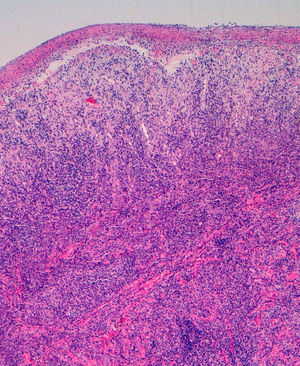

Se solicitaron cultivos para hongos y bacterias que fueron negativos. Se realizó una biopsia cutánea en la que se objetivó la presencia de un intenso infiltrado plasmocitario en la dermis superficial y profunda, de carácter policlonal con técnicas de inmunohistoquímica (figs. 2 y 3).